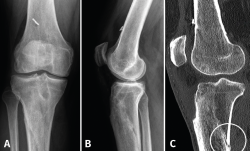

Visto por nosotros a la semana del accidente, presenta un derrame que se evacua y dolor a la palpación del tercio proximal de la tibia con impotencia funcional. La Rx muestra una imagen compatible con fractura metafisodiafisaria proximal de la tibia. Se realiza una TAC (Figura 2) que confirma los hallazgos de la Rx: la fractura afecta a toda la circunferencia, el trazo más distal se encuentra a 37 mm del tornillo distal en la cortical lateral, a 17 mm en la cortical posterior, prácticamente a la altura del tornillo en la cortical medial y sobrepasando levemente el tornillo distal a nivel anterior. Igualmente, se constata una falta de consolidación de la osteotomía de la TTA. Se decide llevar a cabo tratamiento conservador y se inmoviliza con ortesis cruopédica termoplástica, descarga completa con muletas y se inicia magnetoterapia, así como tratamiento con bifosfonatos, calcio y vitamina D.

Figura 2. A y B: la tomografía axial computarizada muestra la fractura metafisodiafisaria no desplazada que afecta a toda la circunferencia y la falta de consolidación de la osteotomía de la tuberosidad tibial anterior.